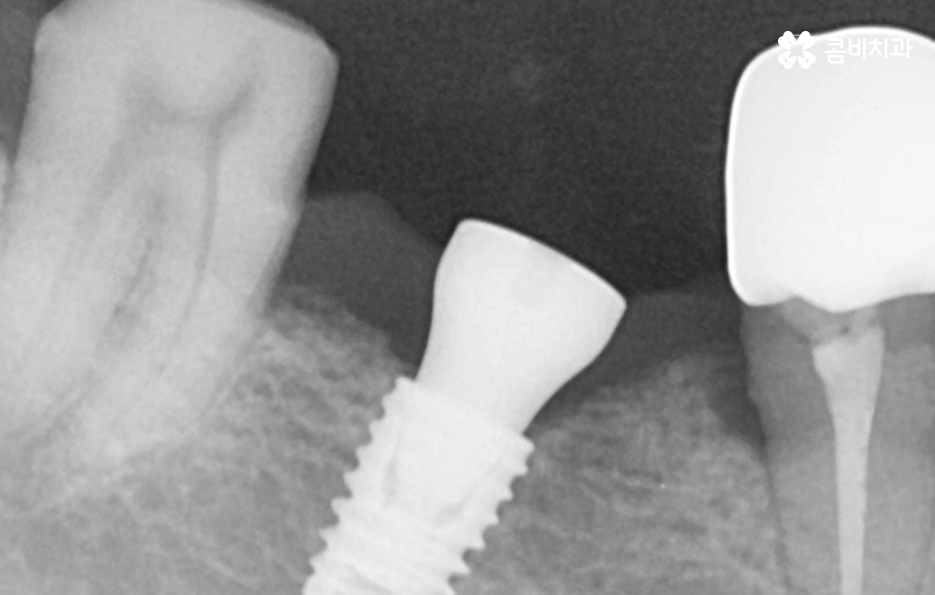

위 케이스의 노인임플란트 치료의 경우 치아의 균열부터 뿌리까지 깊어진 충치, 치주염 까지 복합적인 이유로 치아를 상실하고 여러 개의 임플란트를 식립한 사례라고 할 수 있는데요. 그래도 아직은 잔존하고 있는 치아가 많기 때문에 이미 상실한 치아에는 노인임플란트 각 위치에 맞게 적절한 치료를 받고 나머지의 자연치아에 대해서는 잘 관리하는 것이 중요한 시점이라 할 수 있어요

위 환자분의 케이스는 대부분 어금니 위주로 상실하여 노인임플란트 적절하게 식립하여 어금니의 저작기능을 수복했는데요. 노인임플란트 하면 건강보험에 대한 적용이나 저렴한 치료 비용에 대한 관심을 갖는 경우가 많긴 하지만 연령대에 따라 치아의 잔존율이 크게 급감하는 원인에 대해 잘 알아두시고 이제 치아를 하나 둘씩 잃기 시작했다면 이 시기부터 보다 적극적으로 자연치아를 보존하는 방법을 잘 숙지하시고 특히 주기적으로 치과 검진과 스케일링을 생활화 하는 것이 강조되고 있어요